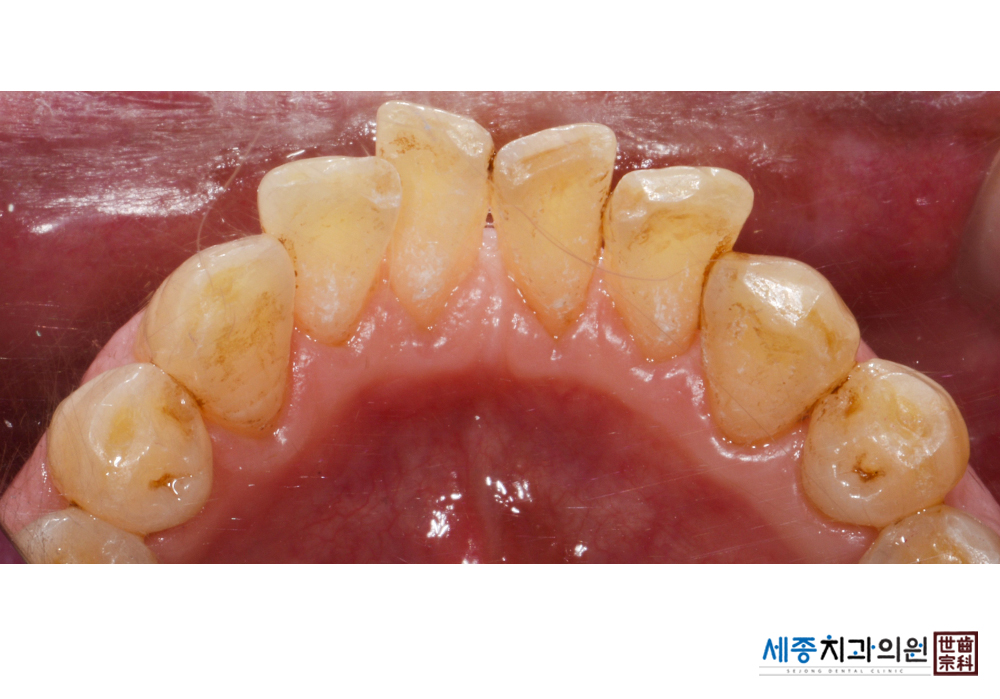

[스케일링] 치주질환 예방 스케일링

치료전 : 2020-02-17

가글마취&저주파 스켈러를 사용한 스케일링